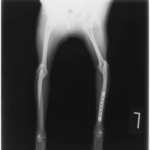

症例3:キルシュナーワイヤーのピンニングによる整復

ペルシャ猫 11ヶ月齢 雄

他院にて左大腿骨遠位の成長板骨折(salter-harrisⅠ型)が認められており、治療相談を目的として来院。当院にて、キルシュナーワイヤーを用いたピンニングにより骨折部位の整復を行いました。術後の経過は良好で、現在も経過観察中です。

術前レントゲン

術後レントゲン